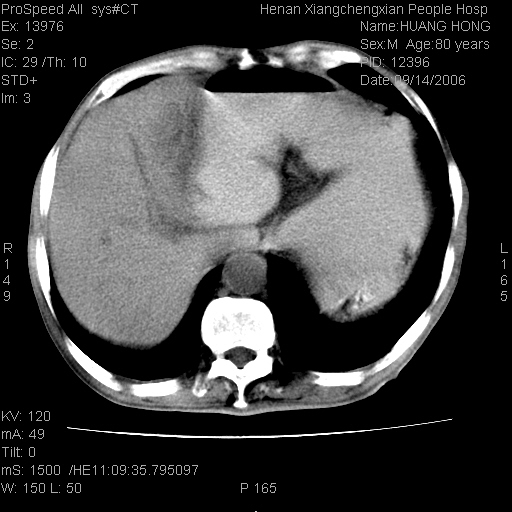

患者, 男, 80岁, 发现上腹部包块1年余,无其它不适.2006-9-14ct片是喝水后扫描2006-9-15ct片没喝水扫描![]() ![]() ![]() ![]() ![]() ![]() ![]() ![]() ![]() ![]() ![]() ![]() ![]() ![]() ![]() ![]() 以上是喝水片 以下是空腹片 ![]() ![]() ![]() ![]() ![]() ![]() ![]() ![]() ![]() ![]() ![]() ![]() ct:胰腺前方、肝脏与胃之间可见巨大类圆形囊性低密度影,大小约152mmx145mmx118mm,上缘平t11椎体上缘,下缘平l3椎体下缘,密度均匀,ct值15hu,其内呈多房分隔,囊壁薄且光滑,边界清晰,周围组织及器官明显受压。肝脏实质内未见异常密度影,胆囊未见异常,胰腺密度未见异常,脾脏大小、形态及密度未见异常,腹膜后间隙未见肿大淋巴结影。 印象:胰腺前方、肝脏与胃之间巨大类圆形囊性低密度影.性质待定。多考虑:.肠系膜巨大囊肿。 守望可可西里发言:支持楼主,考虑肠系膜囊肿,多为小肠系膜。 ysxyy发言:我总觉得这个病人虽然很像肠系膜囊肿,但还是应该强化一下; 下面这几幅图里肿块和主动脉的关系不太清,不知能否除外血管性来源? ![]() ![]() ![]() 病理结果:横结肠系膜间叶瘤.部分区域间质细胞增生活跃. 病理图片 ![]() 良性间叶瘤:是指由两种或两种以上的间叶组织所构成的混合性肿瘤.肿瘤仅发生在腹膜后和肠系膜,.前者较后者多发.良性间叶瘤常发生在肾或四肢,腹膜后较少见,各年龄均可发病.女多与男,预后较好,但术后易复法. 恶性间叶瘤:由两种以上恶性间叶组织成分组成. 光镜:肿瘤由脂肪/血管/平滑肌构成. 原贴地址: http://www.radinet.com.cn/forum_view.asp?forum_id=4&view_id=16217 ok |